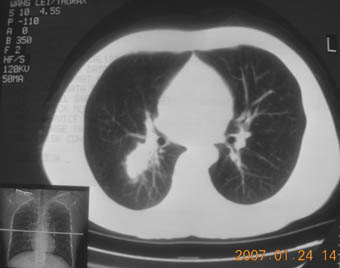

锁骨骨折复查,发现肺内高密度影,行ct检查。

男性,35岁,无任何感觉,无明显发热感冒病史。

病灶呈条片样变,边缘模糊,首先抗炎,然后复查。

病灶多形态:考虑结核可能性大

右肺下叶背段斑片状阴影,边缘模糊,纵隔内未见肿大淋巴结,病人无发热及感冒史,要考虑浸润型肺结核,可结合ppd检查,或短期抗炎治疗复查。

右肺下叶背段长椭圆型病灶,边缘较规则,无明显分叶征、毛刺,远段未见阻塞征象,病灶较松散,纵隔窗明显小于肺窗,年龄35岁,支气管稍示变窄,纵隔内未见明显肿大淋巴结,这些都不支持肿瘤。病人无任何感觉,无明显发热感冒病史,首先考虑结核(也是结核好发部位),慢性炎症不能完全除外。